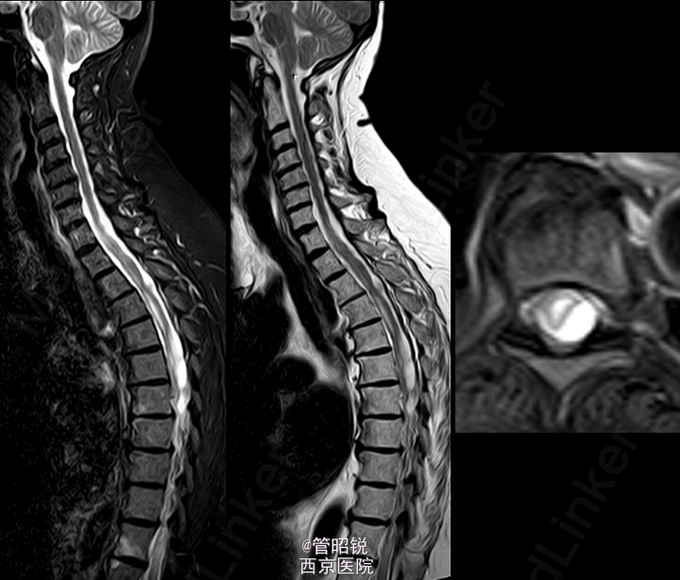

患者,男,71岁,急性头痛和腰痛。 慢性脊髓囊性蛛网膜炎是蛛网膜下腔出血的罕见并发症。此并发症被认为是由于溶血导致的蛛网 膜炎性反应,导致其纤维化和脊膜的继发性增厚,包括硬脑膜。纤维可形成囊腔包裹脑脊液,从而压迫脊髓,引起脊髓病和脊髓空洞积水征。一般保守治疗或者手术 CT显示轻微的脑室内出血,另外,在部分脑裂出可见模糊的高密度影,提示蛛网膜下腔出血。DSA双侧大脑前动脉狭窄。T1WI显示胸腰段脊髓腔内出血,定位在蛛网膜下。随访2年后,显示蛛网膜下的腔隙在脊髓表面形成扇贝样改变。随访3年腔隙仍然存在,以致脊髓表面继发性畸形。(来源于AJNR)